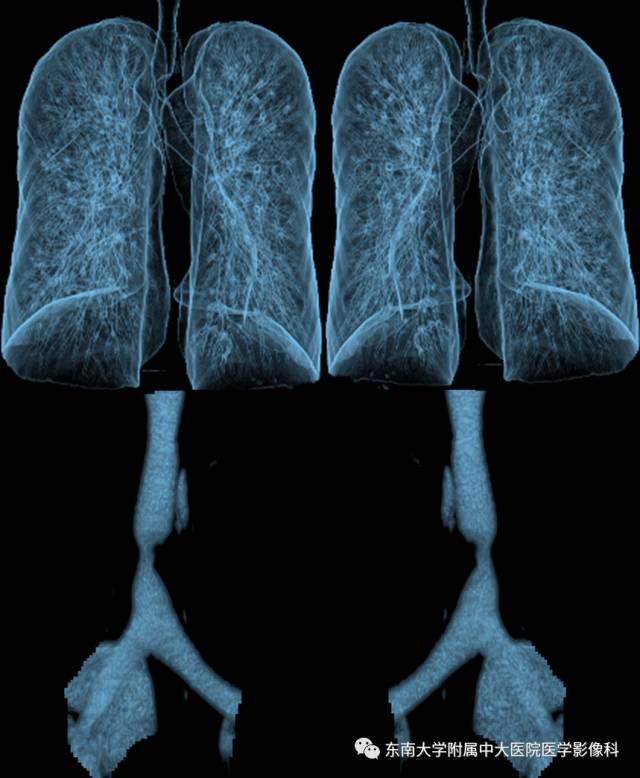

病例2

病史

女,65岁,因“气喘、气促半年余”入院。

CT

增强